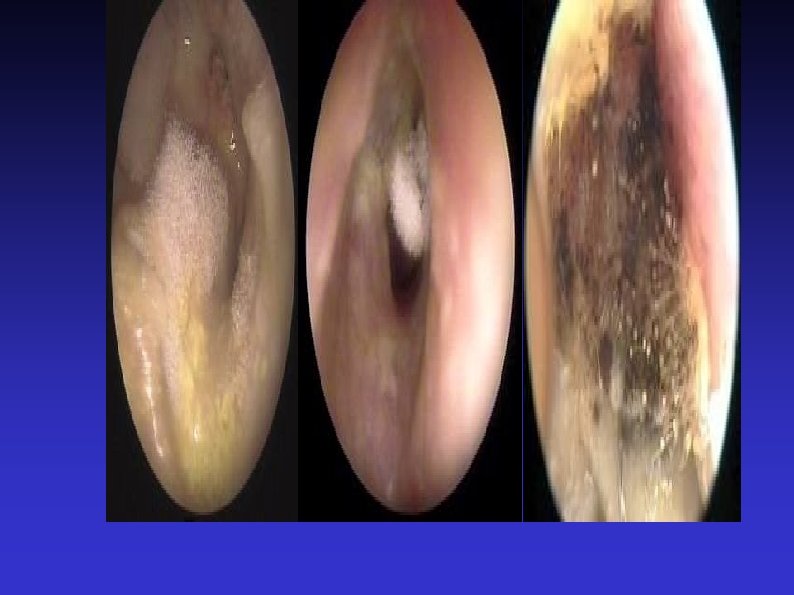

Examination of the Ear 6) Inspect the external auditory meatus Pull pinna upwards, outwards and backwards In infants downwards and backwards In children pull backwards Otorrhoea and otomycosis Canal stenosis Exostoses and osteomas

Examination of the Ear 7) Otoscopic examination The lateral process and handle of the malleus lie towards the centre of the tympanic membrane Four quadrants Perforation Central or marginal What can be seen through it Mastoid cavity Dry Wet, inflamed